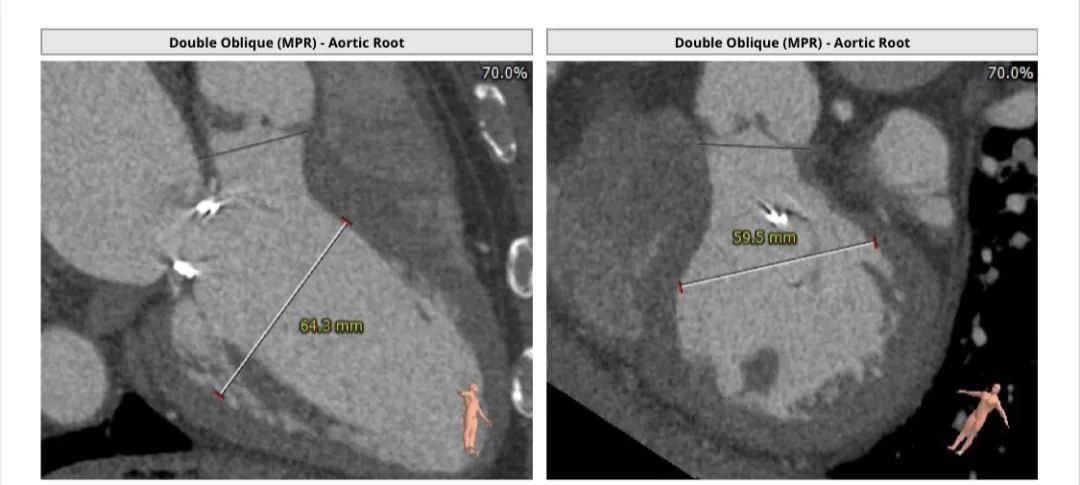

CT评估报告

瓣环平均直径:27.0 mm,左室流出道平均直径:26.8 mm。

升主动脉未见明显扩张,心脏角度:33°。

左冠高度:18.3 mm,右冠高度:17.1 mm。

左室明显增大。

优选右股入路,二尖瓣与主动脉瓣角度:127°。